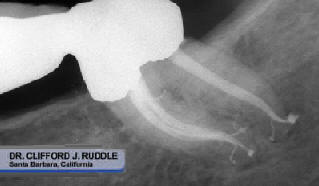

- Kuttler

S: Profesor Asociado de Endodoncia, Universidad Nova SE (Fort

Lauderdale, FL, EE.UU.), abril de 2009. Mostró la eficacia del EndoActivator

en eliminar la capa

de barrillo, biofilm y la apertura de los túbulos dentinarios, en los conductos mesiales curvos

en molares mandibulares

(Figura 6).